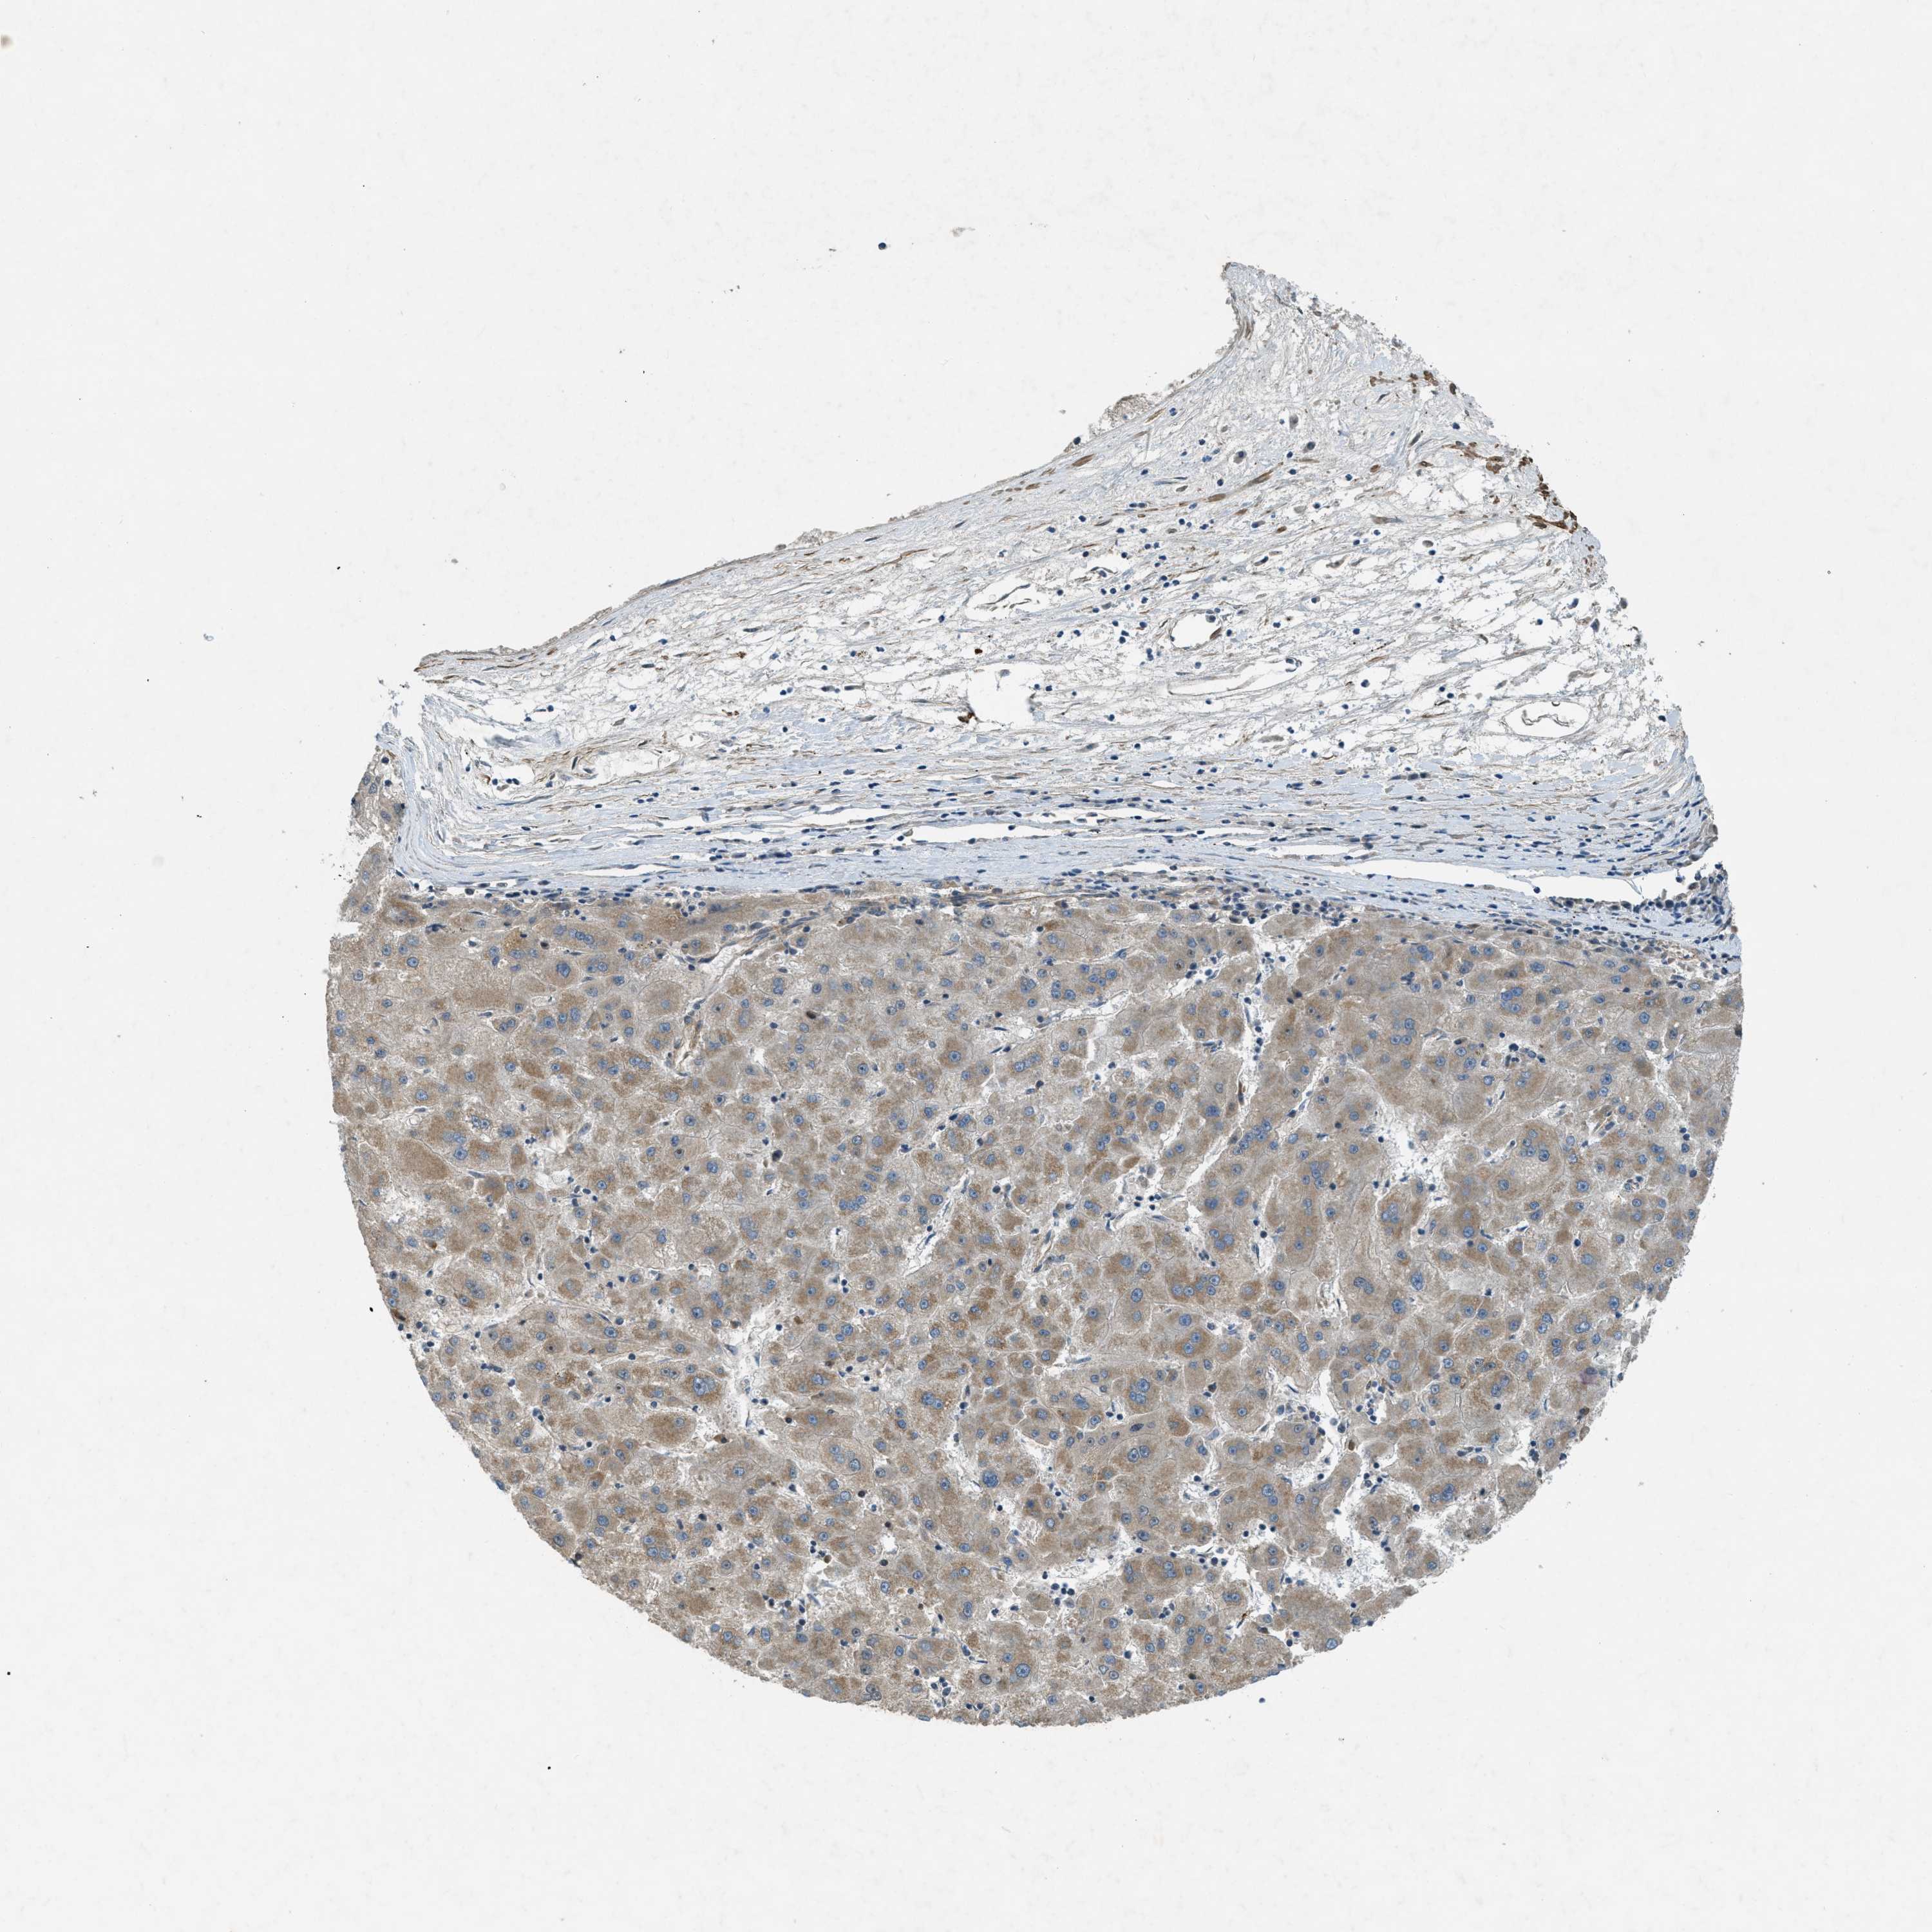

LIVER CANCER - Protein expressioni

A mouse-over function shows sample information and annotation data. Click on an image to view it in a full screen mode. Samples can be filtered based on level of antibody staining by selecting one or several of the following categories: high, medium, low and not detected. The assay and annotation is described here.

Note that samples used for immunohistochemistry by the Human Protein Atlas do not correspond to samples in the TCGA dataset.

Antibody stainingi

Antibody staining in the annotated cell types in the current human tissue is reported as not detected, low, medium, or high, based on conventional immunohistochemistry profiling in selected tissues. This score is based on the combination of the staining intensity and fraction of stained cells.

Each image is clickable and will lead to virtual microscopy that enables deeper exploration of all samples and also displays staining intensity scores, fraction scores and subcellular localization as well as patient and tissue information for each sample.

Antibody HPA004811

Antibody HPA017066

Staining

High

Medium

Low

Not detected

Intensity

Strong

Moderate

Weak

Negative

Quantity

>75%

75%-25%

<25%

None

Location

Nuclear

Cytoplasmic/membranous

Cytoplasmic/membranous,nuclear

Cholangiocarcinoma

Carcinoma, Hepatocellular, NOS